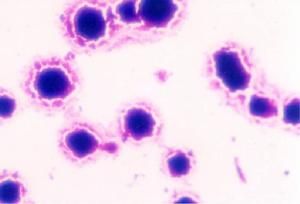

支原體分化 大多數皆性厭氧,有些菌株在初分離時加入5%CO2生長更好。生長緩慢,在瓊脂含量較少的固體培養基上孵育2~3天出現典型的“荷包蛋樣”菌落:圓形(直徑10~16um),核心部分較厚,向下長入培養基,周邊為一層薄的透明顆粒區。此外,支原體還能在雞胚絨毛尿囊膜或培養細胞中生長。

支原體用普通染色法不易著色,用姬姆薩染色很淺,革蘭氏染色為陰性。支原體可在雞胚絨毛尿囊膜上或細胞培養中生長。用培養基培養。營養要求比細菌高。由於它沒有細胞壁,因此對影響細胞壁合成的抗生素,如青黴素等不敏感,但紅黴素、四環素、卡那黴素、鏈黴素、氯黴素等作用於核蛋白體的抗生素,可抑制或影響支原體的蛋白質合成,有殺傷支原體作用,支原體對熱抵抗力差,通常55℃經15分鐘處理可使之滅活。石碳酸,來蘇兒易將其殺死。在培養基中置入脲素並以硫酸錳作指示劑極易與其他支原體作出鑑別。

支原體(Mycoplasmal)是目前所能發現的能在無生命培基中生長繁殖的最小的微生物。 支原體體形多樣,基本為球形,亦可呈球桿狀或絲狀,其菌落呈針尖大小,故又稱之為微小支原體。支原體特點是無細胞壁及前體,細胞器極少。DNA的G C含量低,菌體內具有非常小的染色體組,其分子量約為45×108,菌體細胞大小約為0.2-0.3μm,很少超過1.0μm。由三層蛋白質和脂質組成的膜樣結構以及一層類似毛髮結構組成。支原體由二分裂繁殖,形態多樣。支原體用普通染色法不易著色,用姬姆薩染色很淺,革蘭氏染色為陰性。支原體可在雞胚絨毛尿囊膜上或細胞培養中生長。用培養基培養。營養要求比細菌高。由於它沒有細胞壁,因此對影響細胞壁合成的抗生素,如青黴素等不敏感,但紅黴素、四環素、卡那黴素、鏈黴素、氯黴素等作用於核蛋白體的抗生素,可抑制或影響支原體的蛋白質合成,有殺傷支原體作用,支原體對熱抵抗力差,通常55℃經15分鐘處理可使之滅活。石碳酸,來蘇兒易將其殺死。在培養基中置入脲素並以硫酸錳作指示劑極易與其他支原體作出鑑別。